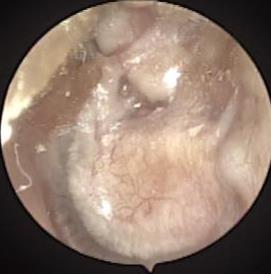

• 耳内镜下耳屏软骨-软骨膜鼓膜修补术后的短期疗效观察

2025, 31(6):1-8. DOI: 10.12235/E20240626

摘要 (319) HTML (229) PDF 4.57 M (181) 评论 (0) 收藏

摘要:目的 探讨耳内镜下耳屏软骨-软骨膜鼓膜修补术后的短期疗效。方法 回顾性分析2019年9月-2022年8月该院收治的78例鼓膜穿孔患者的临床资料,患者均采用耳内镜下鼓膜修补术。术后随访3个月,观察鼓膜形态和穿孔愈合情况,记录内镜图像、干耳时间、术前术后听力及耳鸣情况,以及外耳道狭窄等并发症的发生率。结果 术后3个月,鼓膜穿孔愈合率为97.44%(76/78),愈合良好,平均气导听阈较术前明显改善,气骨导间距较术前明显缩小,耳鸣较术前明显改善,差异均有统计学意义(P<0.05)。干耳时间为(4.21±1.12)周。术后出现肉芽5例,再穿孔2例,真菌感染2例,术腔感染、耳屏感染、外耳道狭窄和切口瘢痕各1例,所有患者术后均未发生面神经麻痹和感音神经性聋等严重并发症。结论 耳内镜下耳屏软骨-软骨膜鼓膜修补术是一种安全、有效的手术方法。根据术后愈合规律、内镜下鼓膜和外耳道形态特征,可为鼓膜修补术后正常中耳转归和并发症的诊疗,提供临床参考。